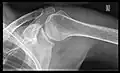

X-ray

Projectional radiography views of the shoulder include:

- AP-projection 40° posterior oblique after Grashey

The body has to be rotated about 30 to 45 degrees towards the shoulder to be imaged, and the standing or sitting patient lets the arm hang. This method reveals the joint gap and the vertical alignment towards the socket.[26]

CR. shoulay film.